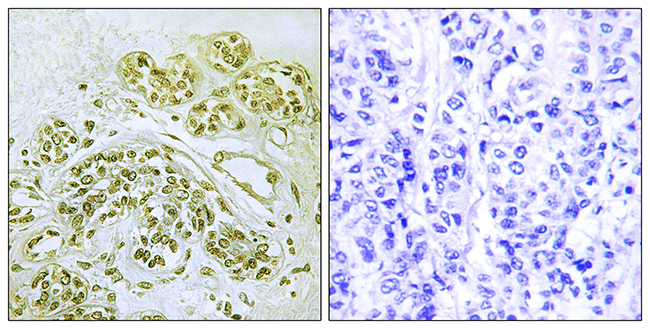

ApplicationsELISA, ImmunoHistoChemistry

ReactivityHuman, Mouse, Rat

ApplicationsELISA, ImmunoHistoChemistry

ReactivityHuman, Mouse, Rat

ApplicationsELISA, ImmunoHistoChemistry

ReactivityHuman, Mouse, Rat

ApplicationsELISA, ImmunoHistoChemistry

ReactivityHuman, Mouse, Rat